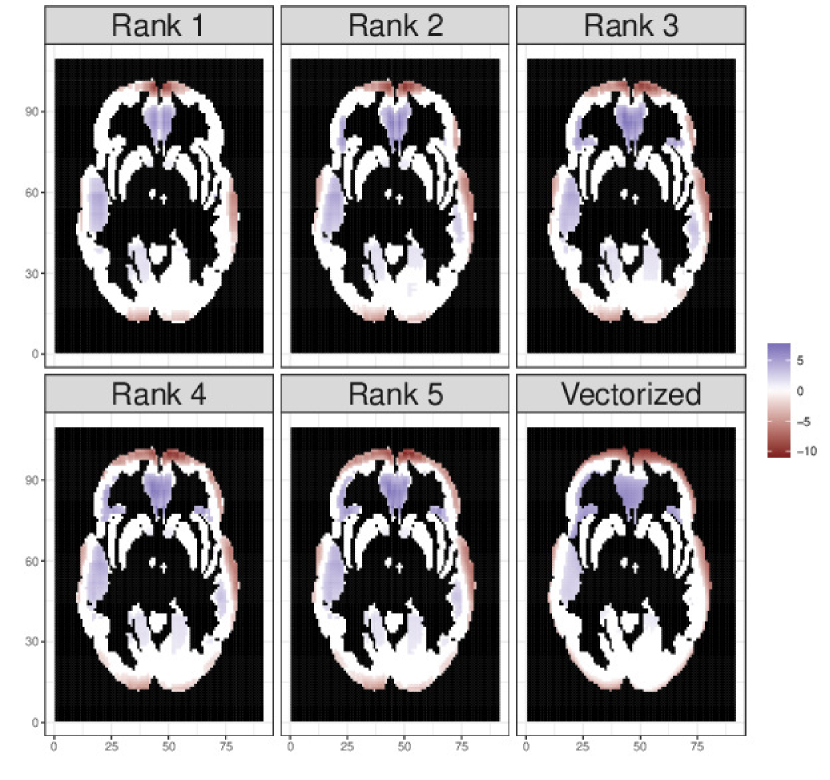

Results Performance measures for all the competitors are summarized in Table 4. The proposed model with various ranks show significant improvement in terms of model fitting statistic over the vectorized-GDP. The tensor models also demonstrate benefit in terms of point estimation and uncertainty quantification. While all tensor models of rank more than 3 show close to nominal coverage, vectorized-GDP suffers from over-coverage with a much wider 95% credible interval. In fact, tensor models corresponding to Rank 3, 4, 5 show excellent detection of activated regions, as is witnessed in Figure 2 and AUC column of Table 4. Although Rank 4 and 5 models demonstrate marginally lower RMSE and improved coverage over the Rank 3 model, Rank 3 model enjoys lowest model fitting statistic. Perhaps, the Rank 4 and 5 models are penalized for having a large number of parameters (see Table 4). Overall, tensor models with rank greater than 222 comprehensively outperform vectorized-GDP as competitors.

The posterior median tensors 𝐁gsubscript𝐁𝑔\mathbf{B}_{g} within the brain have been reorganized to their original positions, and can be seen in Figure 2. Higher values of the coefficient means that there is more blood flow associated with higher levels of perceived risk. Larger positive values indicate that blood flow increases in these regions as risk increases. Larger negative values show regions that exhibit a decrease in blood flow as risk increases, perhaps indicating that blood flows from these regions to the regions with increased blood flow. Similar to the simulation studies, the vectorized GDP model competitor is also fitted to the data to assess the advantages of preserving the tensor structure of the brain image in our proposed model. According to the Deviance Information Criterion (DIC) (Gelman et al., 2014) given in Table 2, Rank 3 is the best performing tensor mixed effect model. Importantly, Rank 3 model also yields considerably smaller DIC value than the vectorized GDP. Figure 2 shows that all the models considered generally agree in terms of the posterior activation results, however, the tensor models provide more differentiated estimates of activation strength than those obtained from the vectorized model, particularly in the Frontal Lobe.

Refer to caption

Figure 2: The posterior median results for the rank 1 through 5 models after using sequential 2-means to classify coefficient values as zero or nonzero. For comparison, vectorized model estimate is also included. Black regions were not analyzed, as they were not included in any regions in the Montreal Neurological Institute Atlas.